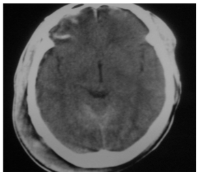

Computed Tomography Findings In Head Trauma In Sokoto (North Western Nigeria)

Dr. K. Isyaku, DR.S. A. Sai'idu, Dr. A. M. TABARI (Author)

8-13

Views | PDF/EPUB Downloads : 59 / 21

DOI: https://doi.org/10.82235/wajr.vol13no1.163